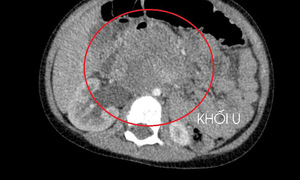

A 56-year-old male patient, experiencing right upper quadrant pain for over one month, was diagnosed with primary hepatic leiomyosarcoma – a type of cancer with only about 70 cases recorded globally.